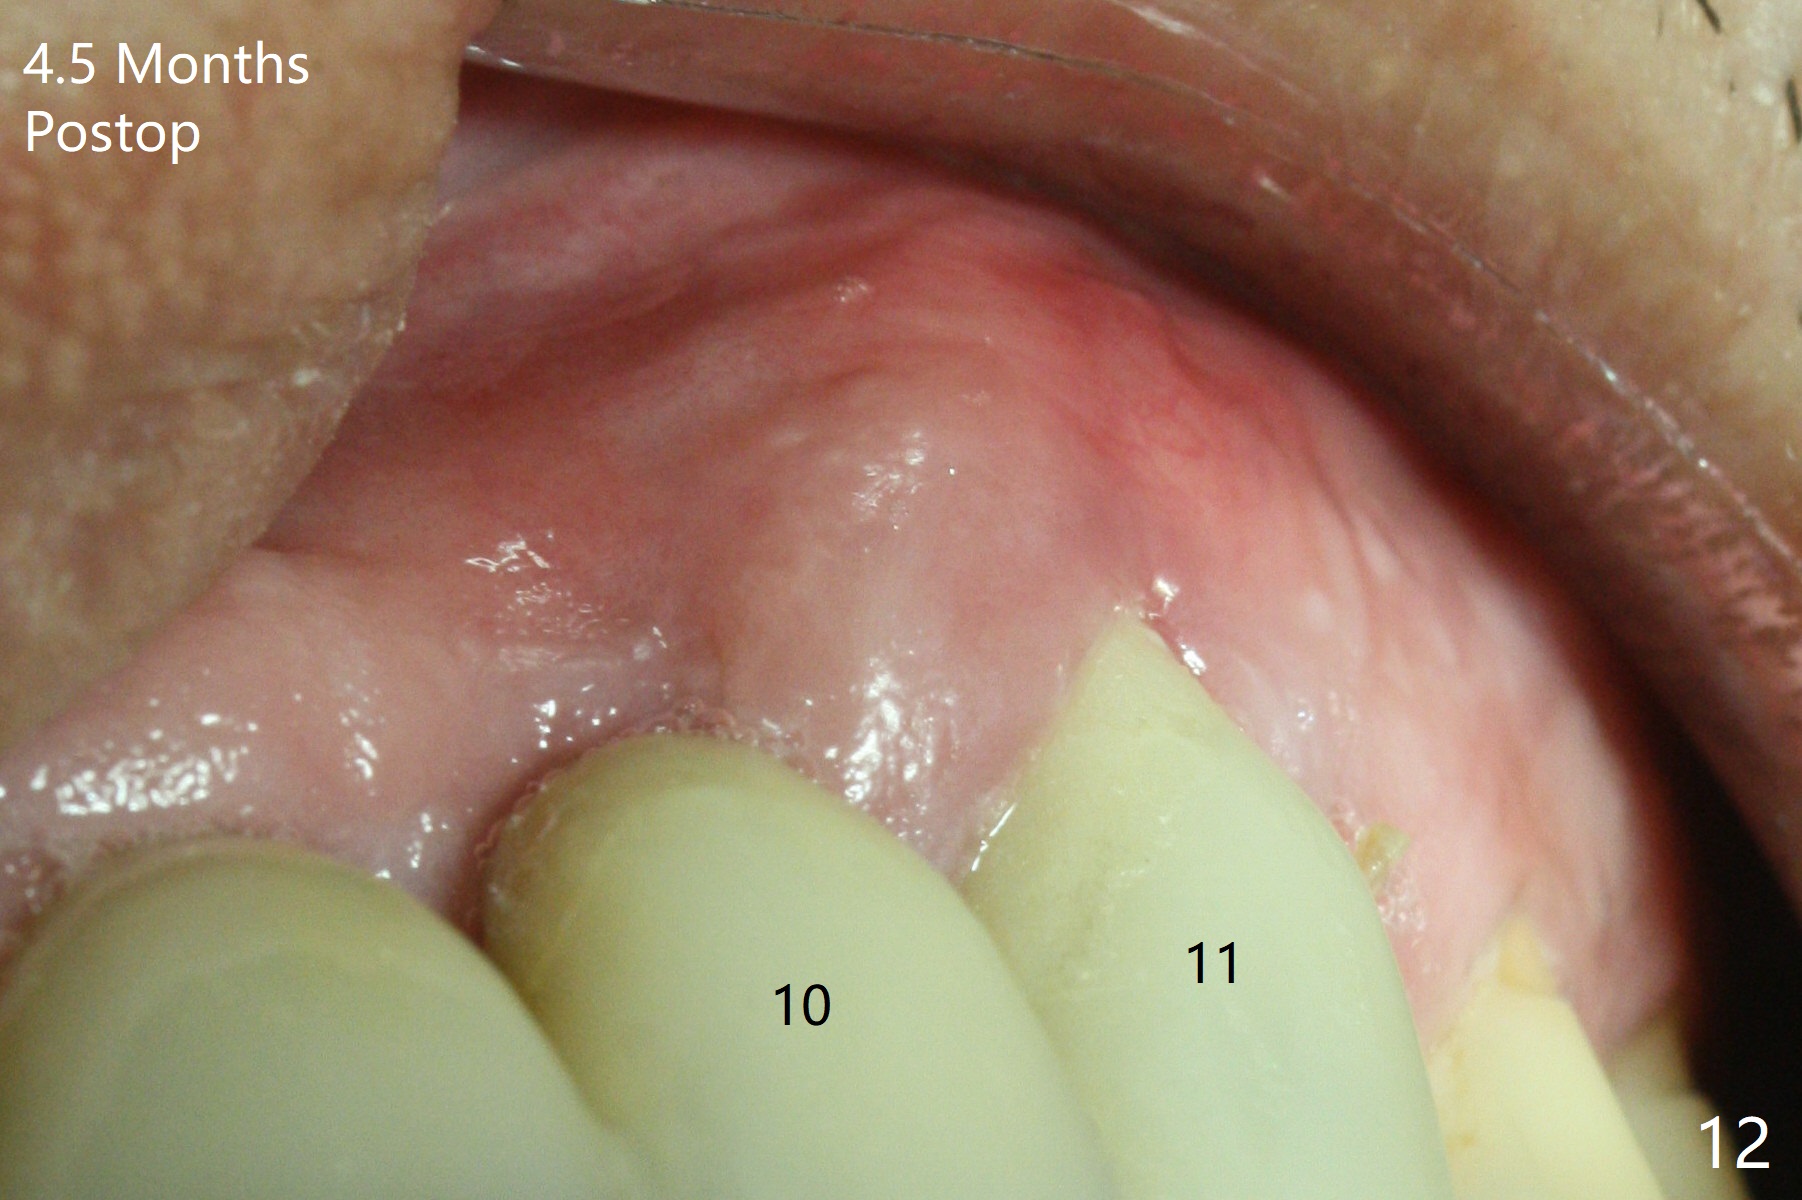

The buccal plate at #10 undergoes atrophy 9 months post immediate implant (Fig.1 *). To prevent the same post-extraction complication at #11, a technique called socket shield is going to be adopted. The buccal portion of the root (Fig.2-6 R, half-moon shaped) remains in place while a 3.5x13 mm implant is placed in the palatal portion of the socket (>50 Ncm). In fact the root is trimmed slightly subcrestal (Fig.6 C). It is assumed that there will be no or minimal bone resorption as long as the periosteum between the buccal plate and the remaining buccal root is not disturbed after tooth removal. After placement of a 4.5x15 degrees A (2mm) angled abutment and Vanilla graft (Fig.7 *), an immediate provisional is fabricated (using a central incisor crown form for #10 because of extra wide space of #11, Fig.8). There is no buccal plate atrophy at the canine 11 days postop (Fig.9). There is smooth transition from the grafted bone to the native bone 4.5 months postop (Fig.10). The buccal plate remains non-atrophic at the canine 4.5 months postop (Fig.11,12). CT taken 1 month post cementation shows that the implants at #10 and 11 are placed somewhat lingually (Fig.13,14 L (*: socket shield)). Gingival swelling is noted (Fig.15 *) with +Bleeding On Probing (^) 8 months post cementation (at the time of #21/24 impression). It appears that the socket shield (Fig.16 S) causes infection and loss of bone graft (*). The shield will be removed with an oblique accessory incision to save the papilla between #10 and 11 (Fig.17 black line). Prepare PRF for sticky bone (x1).